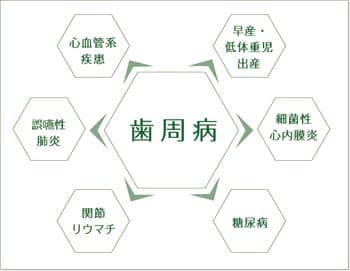

歯周病原菌が全身へと影響をおよぼすメカニズム

歯周病が進行すると歯周ポケットは深くなっていきます。

これに伴い、歯周病原菌の数も増えていき、さらには生体内に侵入した細菌を排除するために白血球が歯周ポケット内へ大量に集積し、免疫・炎症反応が引き起こされます。

その際に作り出されるされるサイトカインなどの物質や歯周病原菌が血液中に入り込み、血行に乗って全身へ移行し、さまざまな疾患と関連していくのです。

※サイトカインとは、抗原が感作リンパ球に結合した時に、このリンパ球から分泌される特殊なたんぱく質